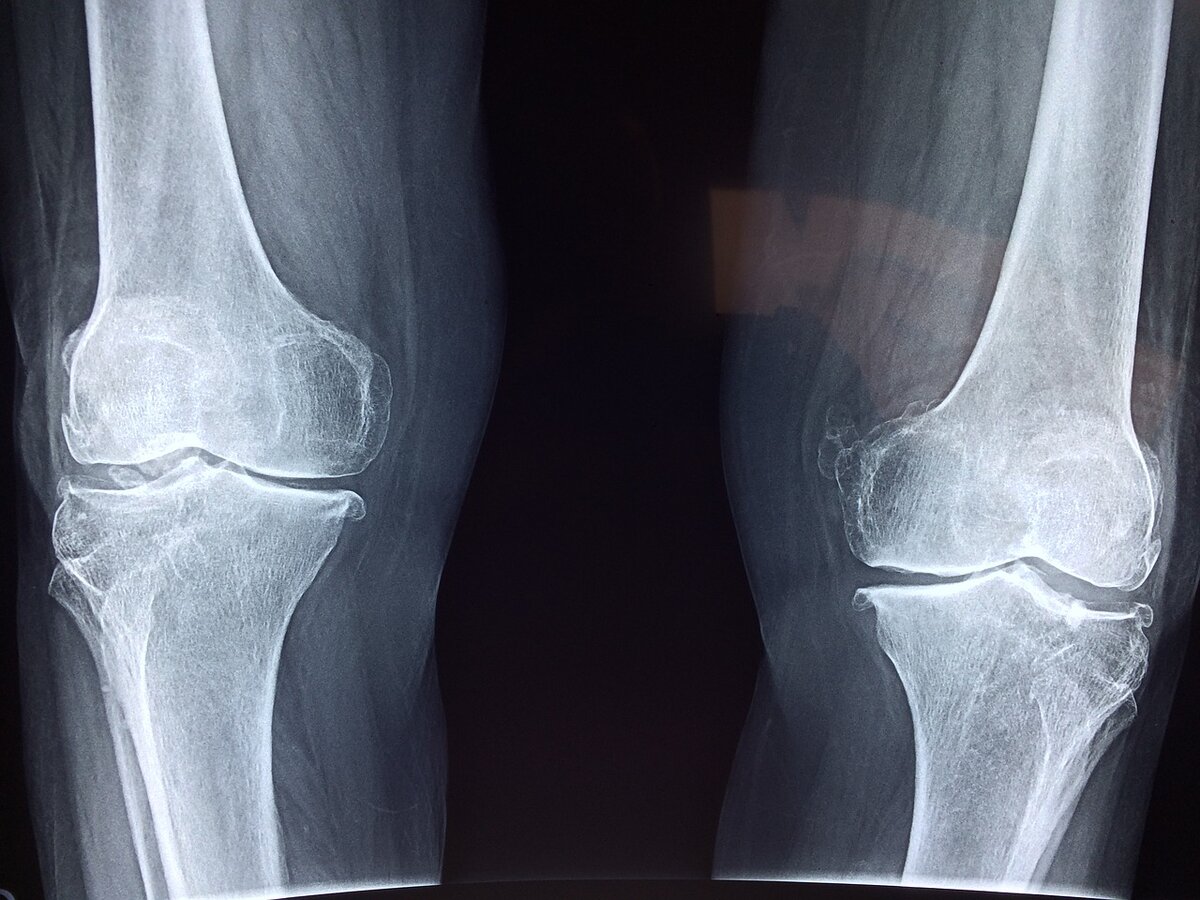

В общем, боль в колене бывает немедленной (острой) или длительной (хронической). Острые боли в колене могут быть вызваны острой травмой или инфекцией. Хронические боли в колене часто являются следствием травм или воспаления (например, артрита), но также могут быть вызваны инфекцией.

Острая боль в колене